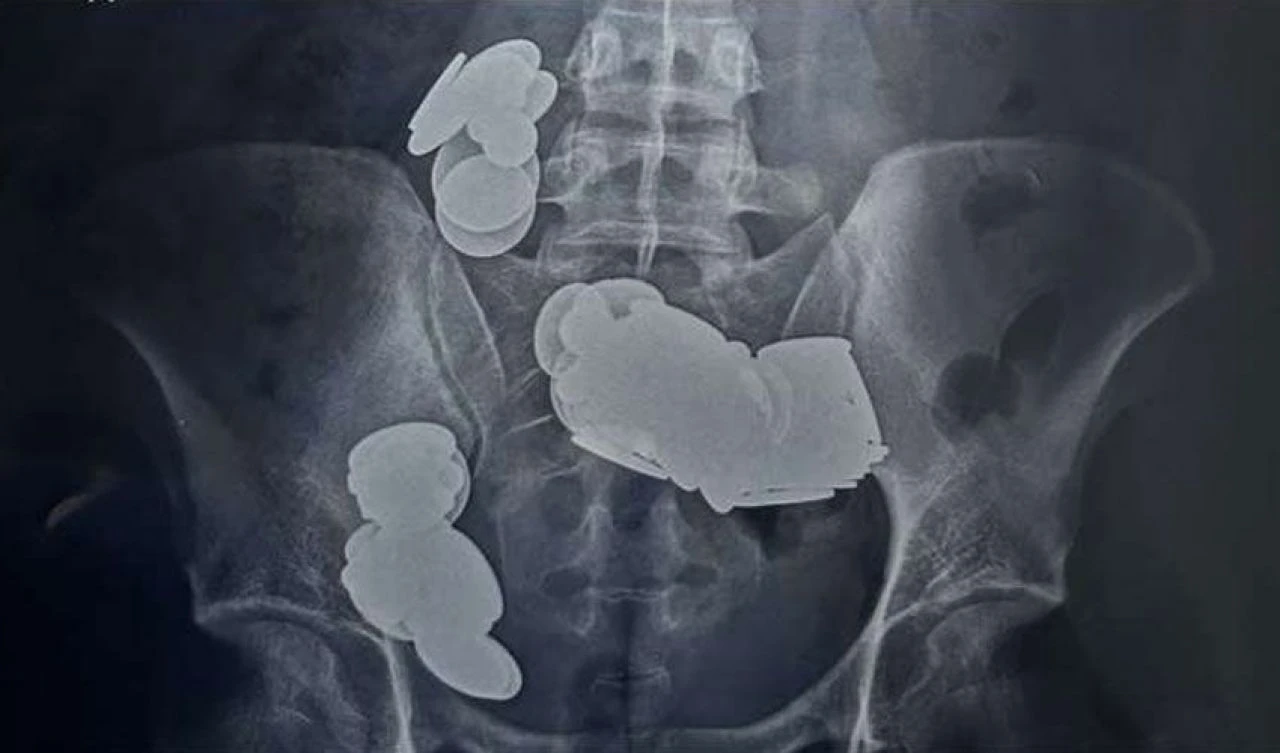

Doktorlar, genci ameliyata aldılar. Ameliyatta, mıknatısların ve madeni paraların ince bağırsakta iki ayrı halka halinde bir araya toplandığını, manyetik kuvvetin onları kilitleyerek bağırsak duvarı boyunca erozyona neden olduğu ortaya çıktı.

Ameliyat başarılı geçti ve gencin 39 bozuk para ve 37 mıknatıs çıkarıldı. Genç, 7 gün daha hastanede tutulmasının ardından taburcu edildi.